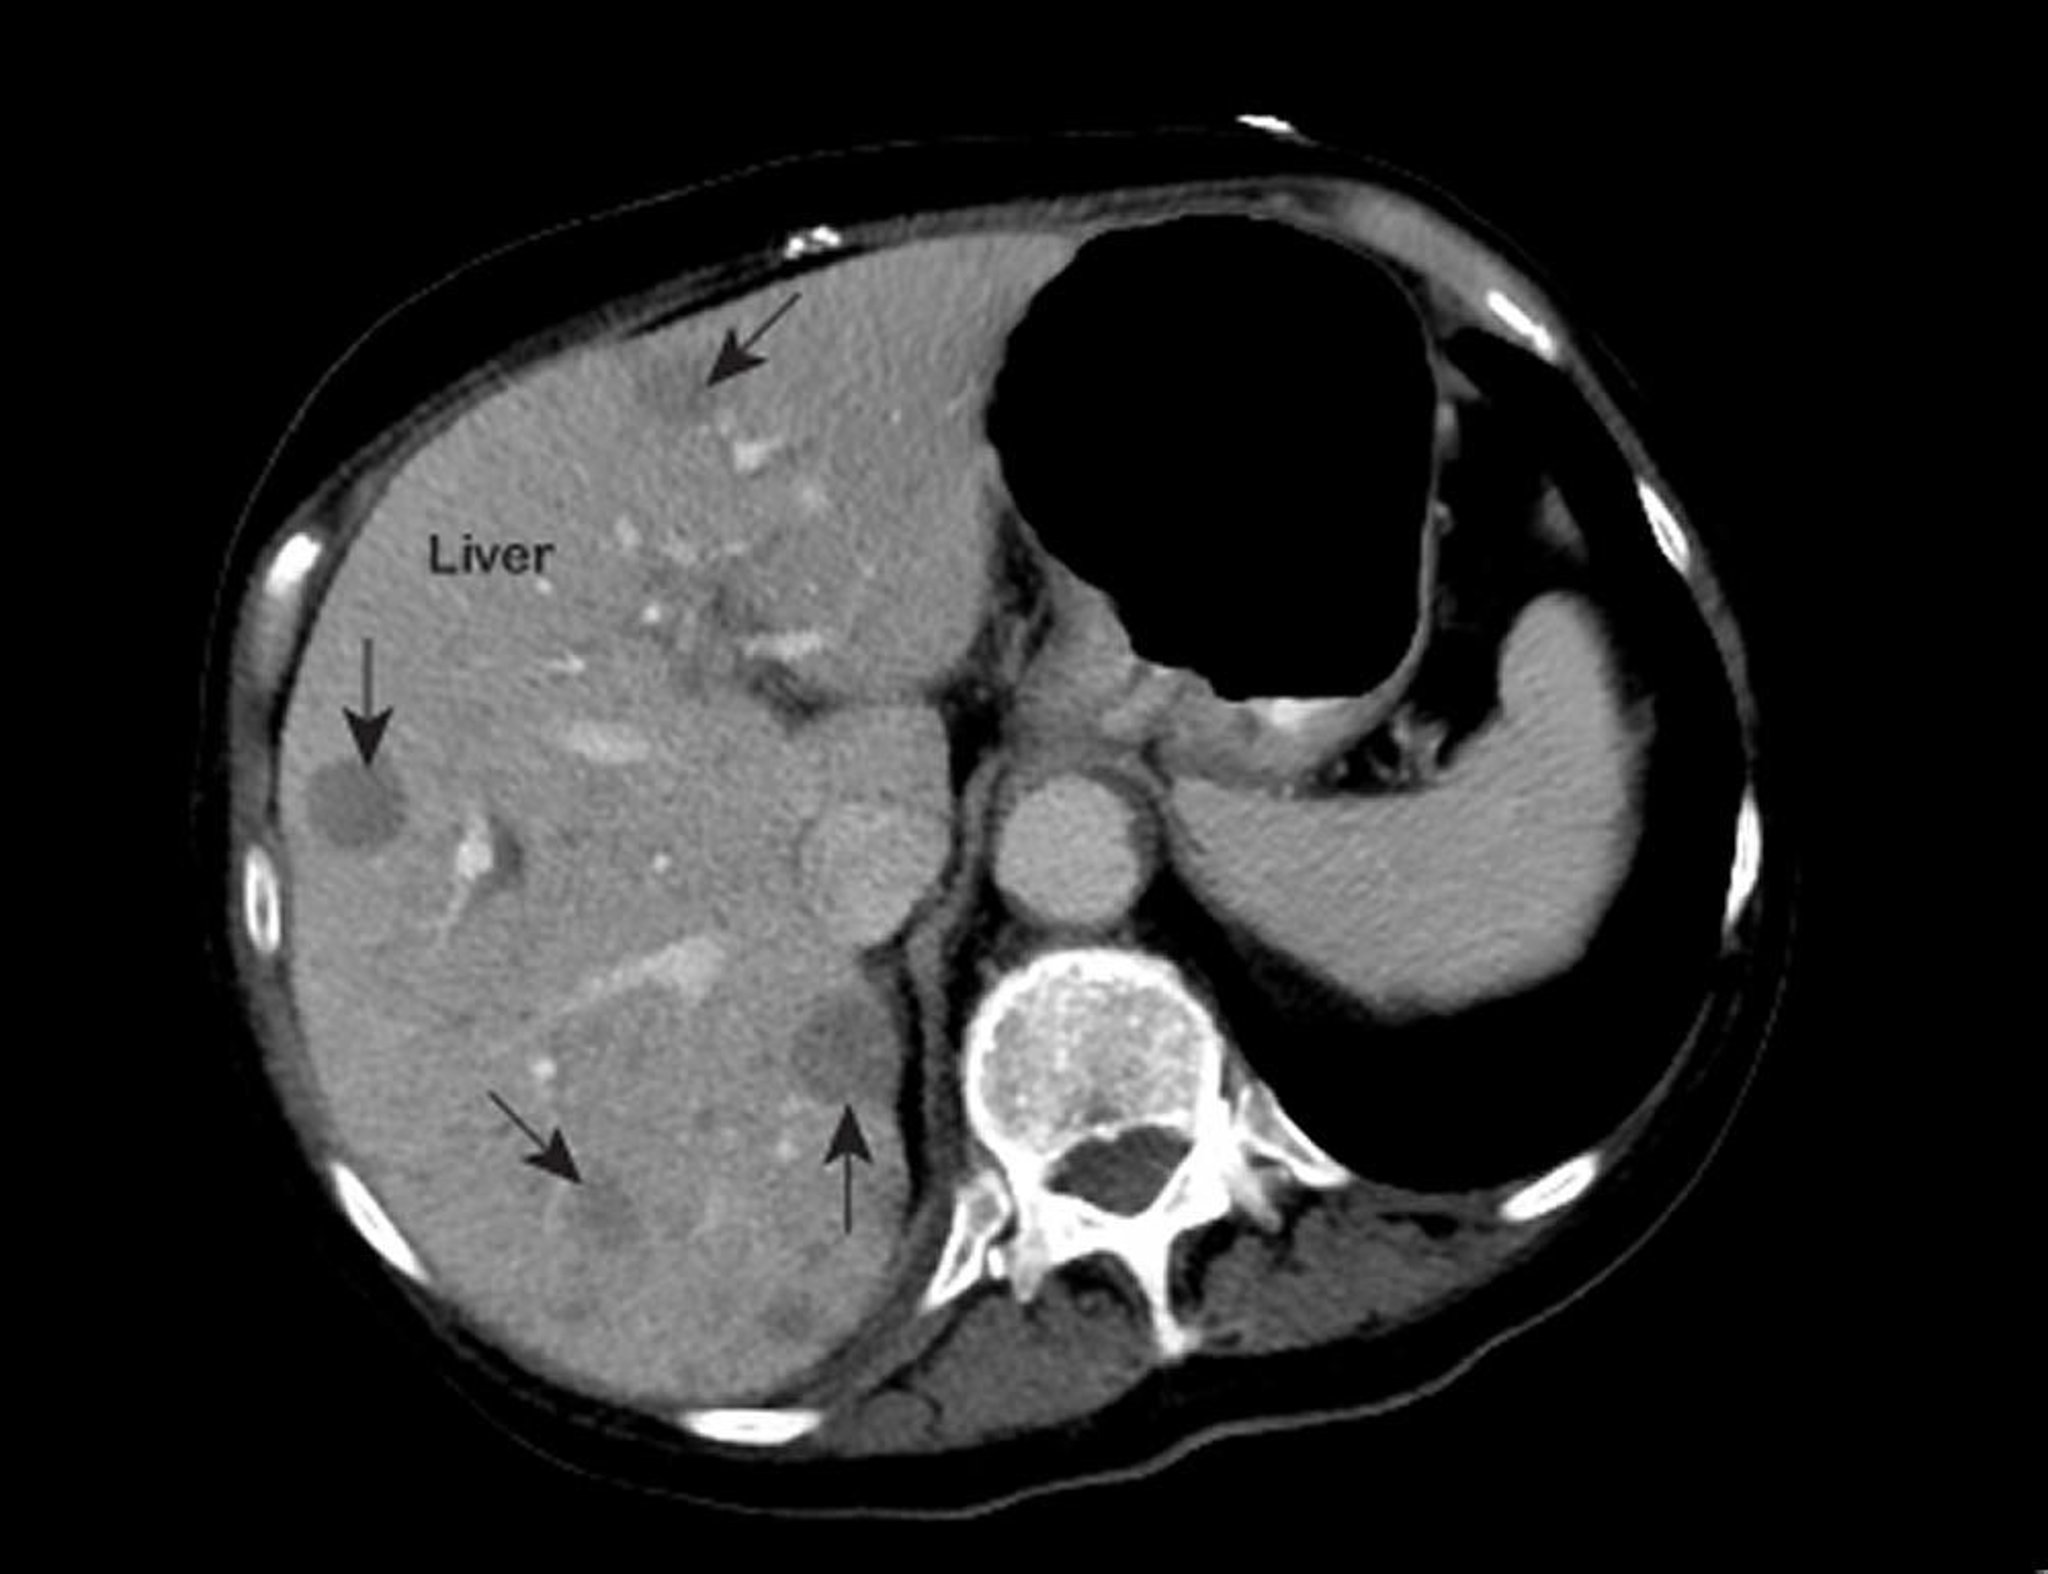

Metástasis tumorales hepáticas

Una resonancia magnética de tórax anormal muestra áreas de baja atenuación (marcadas con flechas) dentro del hígado. Este aspecto es típico del cáncer de hígado metastásico.

Photo courtesy of Patrick O’Kane, MD.